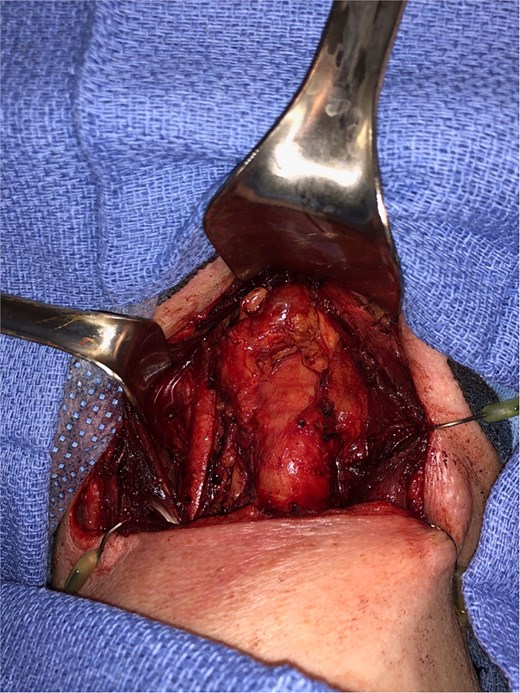

Endocrinology workup revealed calcitonin of 25.4 pg/ml (ref: 0.0–5.1) and CEA of 20.1 ng/ml (ref: 0.0–3.0). The patient denied any family history of thyroid or parathyroid disease or MEN syndromes. She was referred to head and neck surgery and underwent total thyroidectomy with central compartment dissection (Fig. 2).

Intraoperative image, demonstrating a central level 6 neck mass medial to the thymus, following total thyroidectomy.